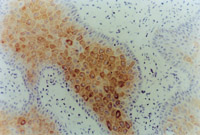

MEBT/MEBO治疗30天后,,,,,,再生修复的上皮组织举行细胞角质素AE3检查为阳性,,,,,,表皮颗粒层细胞质呈棕色染色,,,,,,细胞核呈蓝色(图5-3-9~5-3-6),,,,,,证实为自身再生的复层鳞状上皮。。 。

5-3-9 MEBT/MEBO治疗30天,,,,,,细胞角质素AE3呈阳性。。 。(说明患者烧伤创面是自我再生修复) HE×20

5-3-10 同上  HE×40